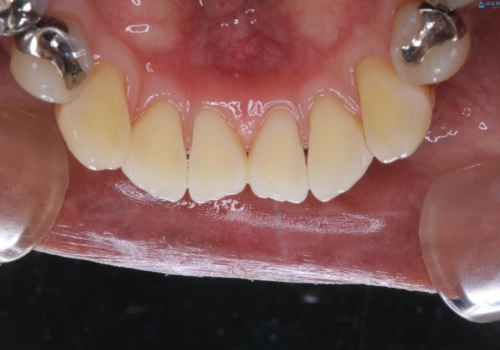

- クリーニングをしてほしいとのことで来院されました。

PMTC60分コースを行いました。

着色がとても多くついていました。

虫歯と着色の色は、同じ黒のため、見分けがつきにくいです。また、着色やプラークで隠れてしまっていることが多々です。

そのため、クリーニングをしっかり行ってから虫歯のチェックをさせていただいています。